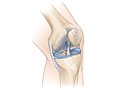

- Find problems in the knee joint,

such as

arthritis, bone tumors, or infection, or damaged

cartilage,

meniscus, ligaments, or

tendons.